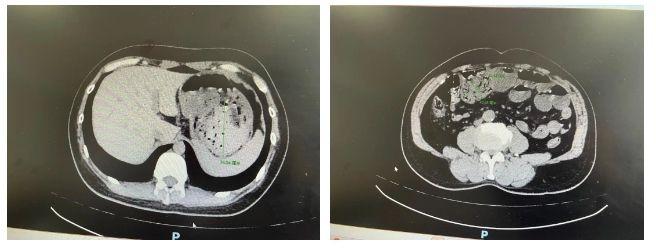

53岁的赵先生(化名)半斤山楂下肚,一天后因为腹痛就医,腹部CT显示胃石,直径约7.5cm;30岁的廖女士(化名)吃了螃蟹后吃山楂,很快也因为上腹部绞痛伴呕吐来到医院就诊,也是胃石作祟,直径约6cm;63岁的李先生(化名)仅被一个柿子就撂倒了,来院就诊时胃石已经下行至肠道,导致小肠部分梗阻……

浙江医院消化内科李楠医师介绍,钱女士的情况比较严重,胃石下行导致其小肠严重梗阻,无奈最后只能接受外科手术,切掉了一段16cm的小肠。

浙江医院消化内科副主任王卫峰主任医师强调,胃石除了造成患者胃部不适,还可能损伤患者的胃黏膜,从而导致胃溃疡的发生。个别情况下,患者还会出现消化道出血,部分胃石还可能通过幽门而进入小肠,从而引起更严重的小肠梗阻。对于较小或较松散的结石,可服用碱性溶液(如小苏打、可乐)中和胃酸、松解结石,最后使碎掉的结石随粪便排出。同时可以应用抑酸药物、胃动力药物、消化酶制剂等治疗。对于较大较坚硬的结石就需要胃镜下取出或者搅碎排出,内镜下难以搅碎的巨大结石或者已经导致穿孔的则需要外科手术。